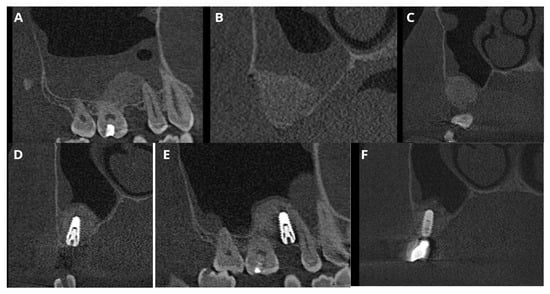

In this case, after removing the osseous ring, the Schneiderian membrane perforation was closed with resorbable polyglycolic acid 5-0 suture (Figure 11) and BloodSTOP™ iX (LifeScience Plus, Mountain View, CA, USA) (Figure 12A) before placing the xenograft with I-PRF (Figure 12B). Nevertheless, the authors find suturing Schneiderian perforation difficult and threatening to advance the perforation dimensions; hence, it is inadvisable for inexperienced surgeons. Xenograft was covered with a collagen membrane Osseoguard Flex (Zimmer Biomet Dental, Biomet 3i, Palm Beach Gardens, FL, USA) and closed with 5-0 nylon sutures (Figure 12C,D). Figure 13 presents post-op CBCT screenshots and radiological follow-up.

Figure 13. Screenshots of the post-op CBCT scans. Immediately after Croco Eye (A,B), 6 months post-op: before (C) and after implant placement (D,E). The latest follow-up was 5 years 2 months post-op with a loaded implant (F). Throughout the follow-up period, no recurrence of the cyst was detected.